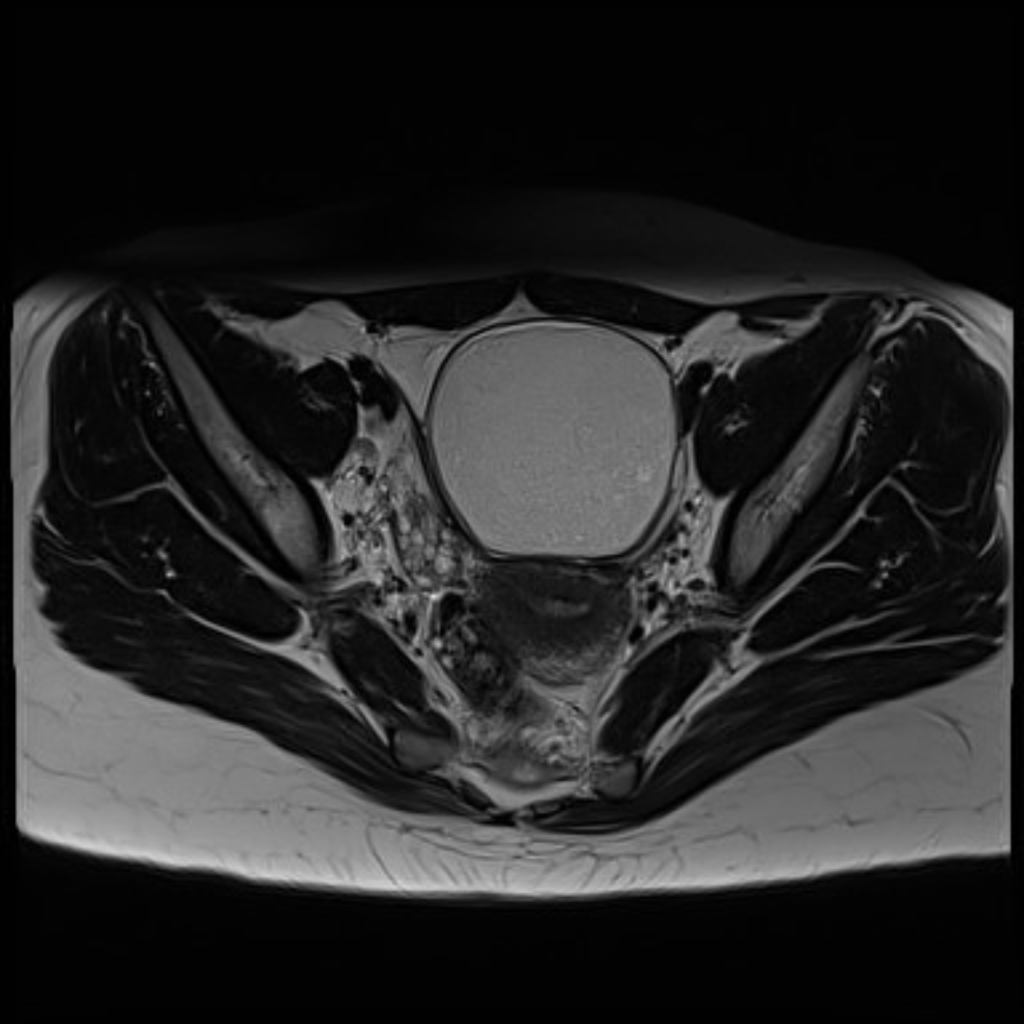

Een paar weken later bekijken we samen de beelden van de echo. Onzeker scrollen we door de foto’s heen, niet echt wetende waar we op moeten letten. En dan zien we het: Een enorme witte bal, op de plek waar je de blaas en de baarmoeder zou verwachten. “Is dat mijn baarmoeder?” Ik weet niet zo goed wat ik moet antwoorden. “Nee, wacht, fucking hell, dat is dat ding.”

Dat ‘ding’ is een tumor. Geen kanker, gelukkig, maar wel degelijk een tumor. Met een omvang van zo’n tien centimeter; zo groot als een honkbal dus. Dat ‘ding’ dat haar baarmoeder, eierstokken, blaas en al het andere dat er nog zit volledig wegdrukt. Geen wonder dat ze constant pijn heeft.

De witte bol in het midden valt moeilijk te missen.

Deze tumor is door een professionele gynaecoloog, die meerdere echo’s bij haar heeft uitgevoerd, compleet over het hoofd gezien. Sterker nog, de tumor is zó groot dat ze het had kunnen en misschien wel moeten voelen bij het inbrengen van de spiraal. Ik heb Skye nog nooit zo boos gezien. “Weet je wat die vrouw nog tegen me zij?” Ik schud mijn hoofd. “Dat ik er zonder die tumor in mijn lichaam weleens minder zwanger uit zou kunnen zien… waar haal je het gore lef vandaan, alsof dat het fucking belangrijkste in de wereld is.”